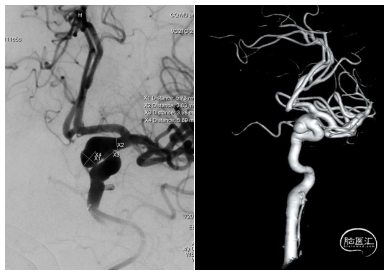

术前DSA:左侧颈内动脉床突旁动脉瘤,形态不规则,大小约5.7mm x 5.9mm。

患者DSA血管造影提示左侧颈内动脉床突旁动脉瘤,动脉瘤形态不规则、瘤颈较宽,具有一定的破裂出血风险,对于破裂风险较高的低Hunt-Hess分级未破裂动脉瘤,建议予以积极治疗从而避免动脉瘤破裂出血造成严重后果。